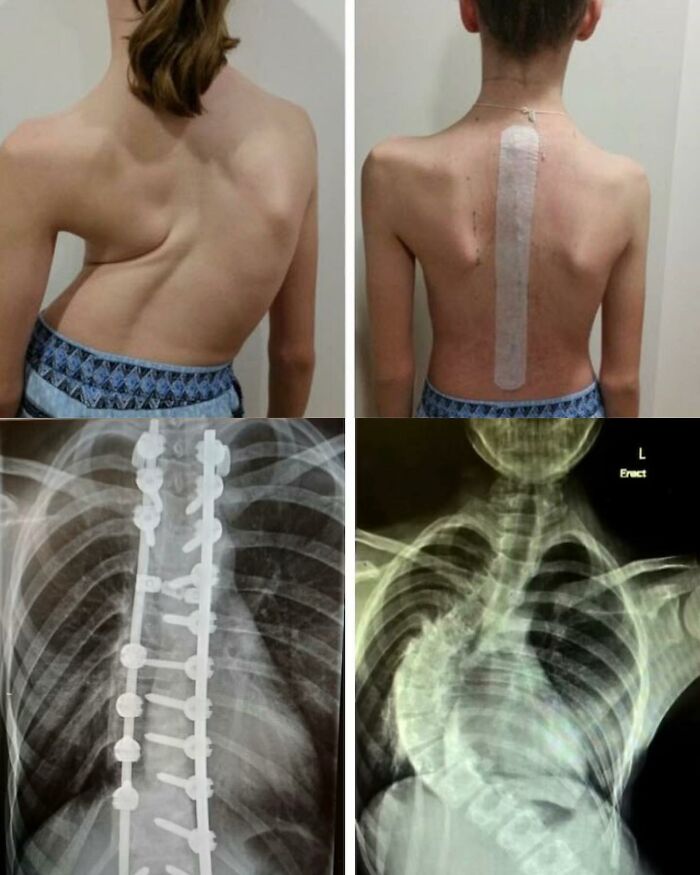

Transforming Curves: From Struggle To Strength - Witness The Journey Of Scoliosis

Scoliosis is characterized by a lateral deviation and rotational deformity of the spine, resulting in an abnormal sideways curvature. It can manifest in different regions of the vertebral column and exhibit varying degrees of severity.

This 13-year-old’s scoliosis was progressing so rapidly that major spinal surgery was her only treatment option. In just over six months, her curve progressed from what was initially 49-degree to a 99-degree curve. The girl now has a combination of titanium rods and screws around her spine. Luckily she fully recovered and got back to her normal activities.

While scoliosis can be caused by conditions such as cerebral palsy and muscular dystrophy, the cause of most scoliosis is unknown. About 3% of adolescents have scoliosis.

Treatment depends on the degree of curve, location, and cause. Minor curves may simply be watched periodically. Management options may involve close observation, utilization of orthotic devices (e.g., braces) for stabilization, or, in severe cases, surgical intervention aimed at rectifying the curvature and achieving spinal stability. The brace must be fitted to the person and used daily until growing stops.

Surgery is usually recommended by orthopedists for curves with a high likelihood of progression (i.e., greater than 45 to 50° of magnitude), curves that would be cosmetically unacceptable as an adult, curves in people with spina bifida and cerebral palsy that interfere with sitting and care, and curves that affect physiological functions such as breathing. To completely straighten a scoliotic spine is usually impossible, but for the most part, significant corrections are achieved.

Credit: Isabel Dayman, Mobile.abc.net.au